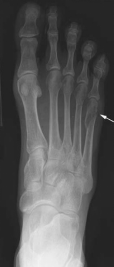

痛风

嘌呤代谢紊乱,以体液、血液中尿酸增加及尿酸盐沉着于各种间叶组织内引起炎症反应

好发于男性,发病高峰40-60岁

以第1跖趾关节最为多见

早期周围软组织肿胀,出现局限骨质硬化,晚期关节面边缘出现囊状、穿凿状骨质缺损,关节间隙可变窄,关节面不光整,晚期骨赘形成可使骨端增大

68Y,M